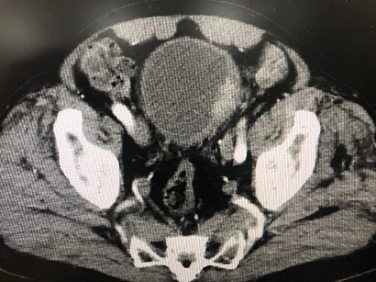

病例四,76岁男性,膀胱肿瘤电切术后2个月,复查CTU提示膀胱癌复发可能,左侧壁不均匀增厚,范围约4cm,尿液TCT+特殊染色提示高级别尿路上皮癌细胞阳性,外院病理切片于本院会诊提示高级别尿路上皮癌(G3),可见广泛固有层侵犯,局灶侵犯固有肌层。行机器人辅助腹腔镜膀胱根治性切除术,盆腔淋巴结清扫术,原位膀胱术,术者:王国良教授。